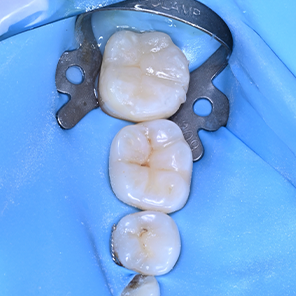

레진빌드업

치과의사의 손길로 빚어내는, 섬세한 치아 수복

레진빌드업은 치과의사가 구강 내에서

직접 치아의 형태를 세심하게 만들어나가는 수복 방식입니다.

자연치아의 구조를 모방(biomimetic) 하여

신중하게 접착하는 과정을 거치며,

본래 치아와 조화롭게 기능할 수 있도록 돕습니다.

레진빌드업 치료 후